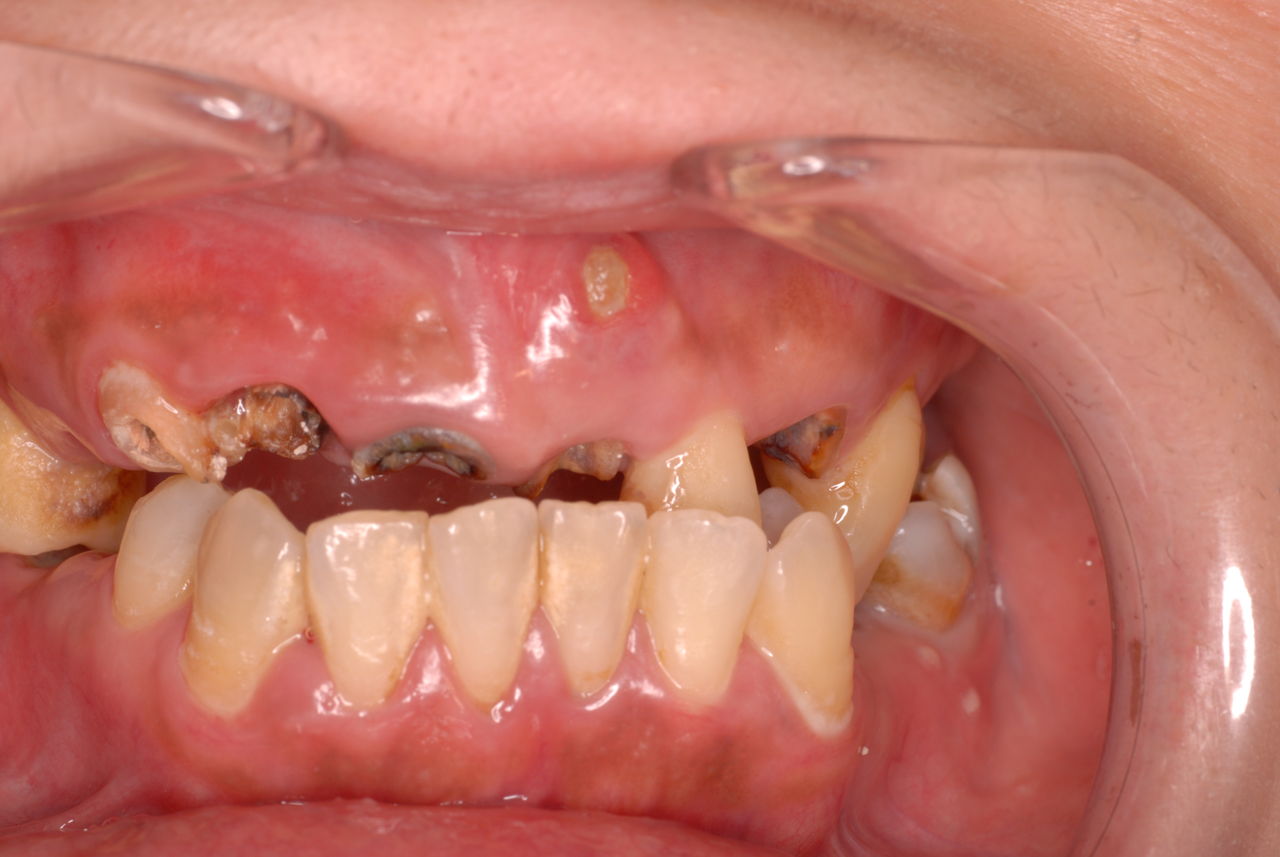

今でさえすごい虫歯でも治療も受けずにいる方がたまにいます。

其の方達は、男性でも女性でも素直な、疑いを持たない方々かもしれません。

歯科医を疑わず何年も通い続けて歯がなくなる方々です。或いは変なことを言われそれを信じ込んで(ご本人の聞き間違いかもしれませんが)怖くていけなくなったとか、あまりにもひどく歯医者に見せるのも恥ずかしく酷い状態になったとかいう方方です。

30代の男性の方です。

入れ歯を入れていました。歯科医院で歯を抜けず仕方なく入れ歯にしたとか。何とかならないものだったのか悔やまれました。